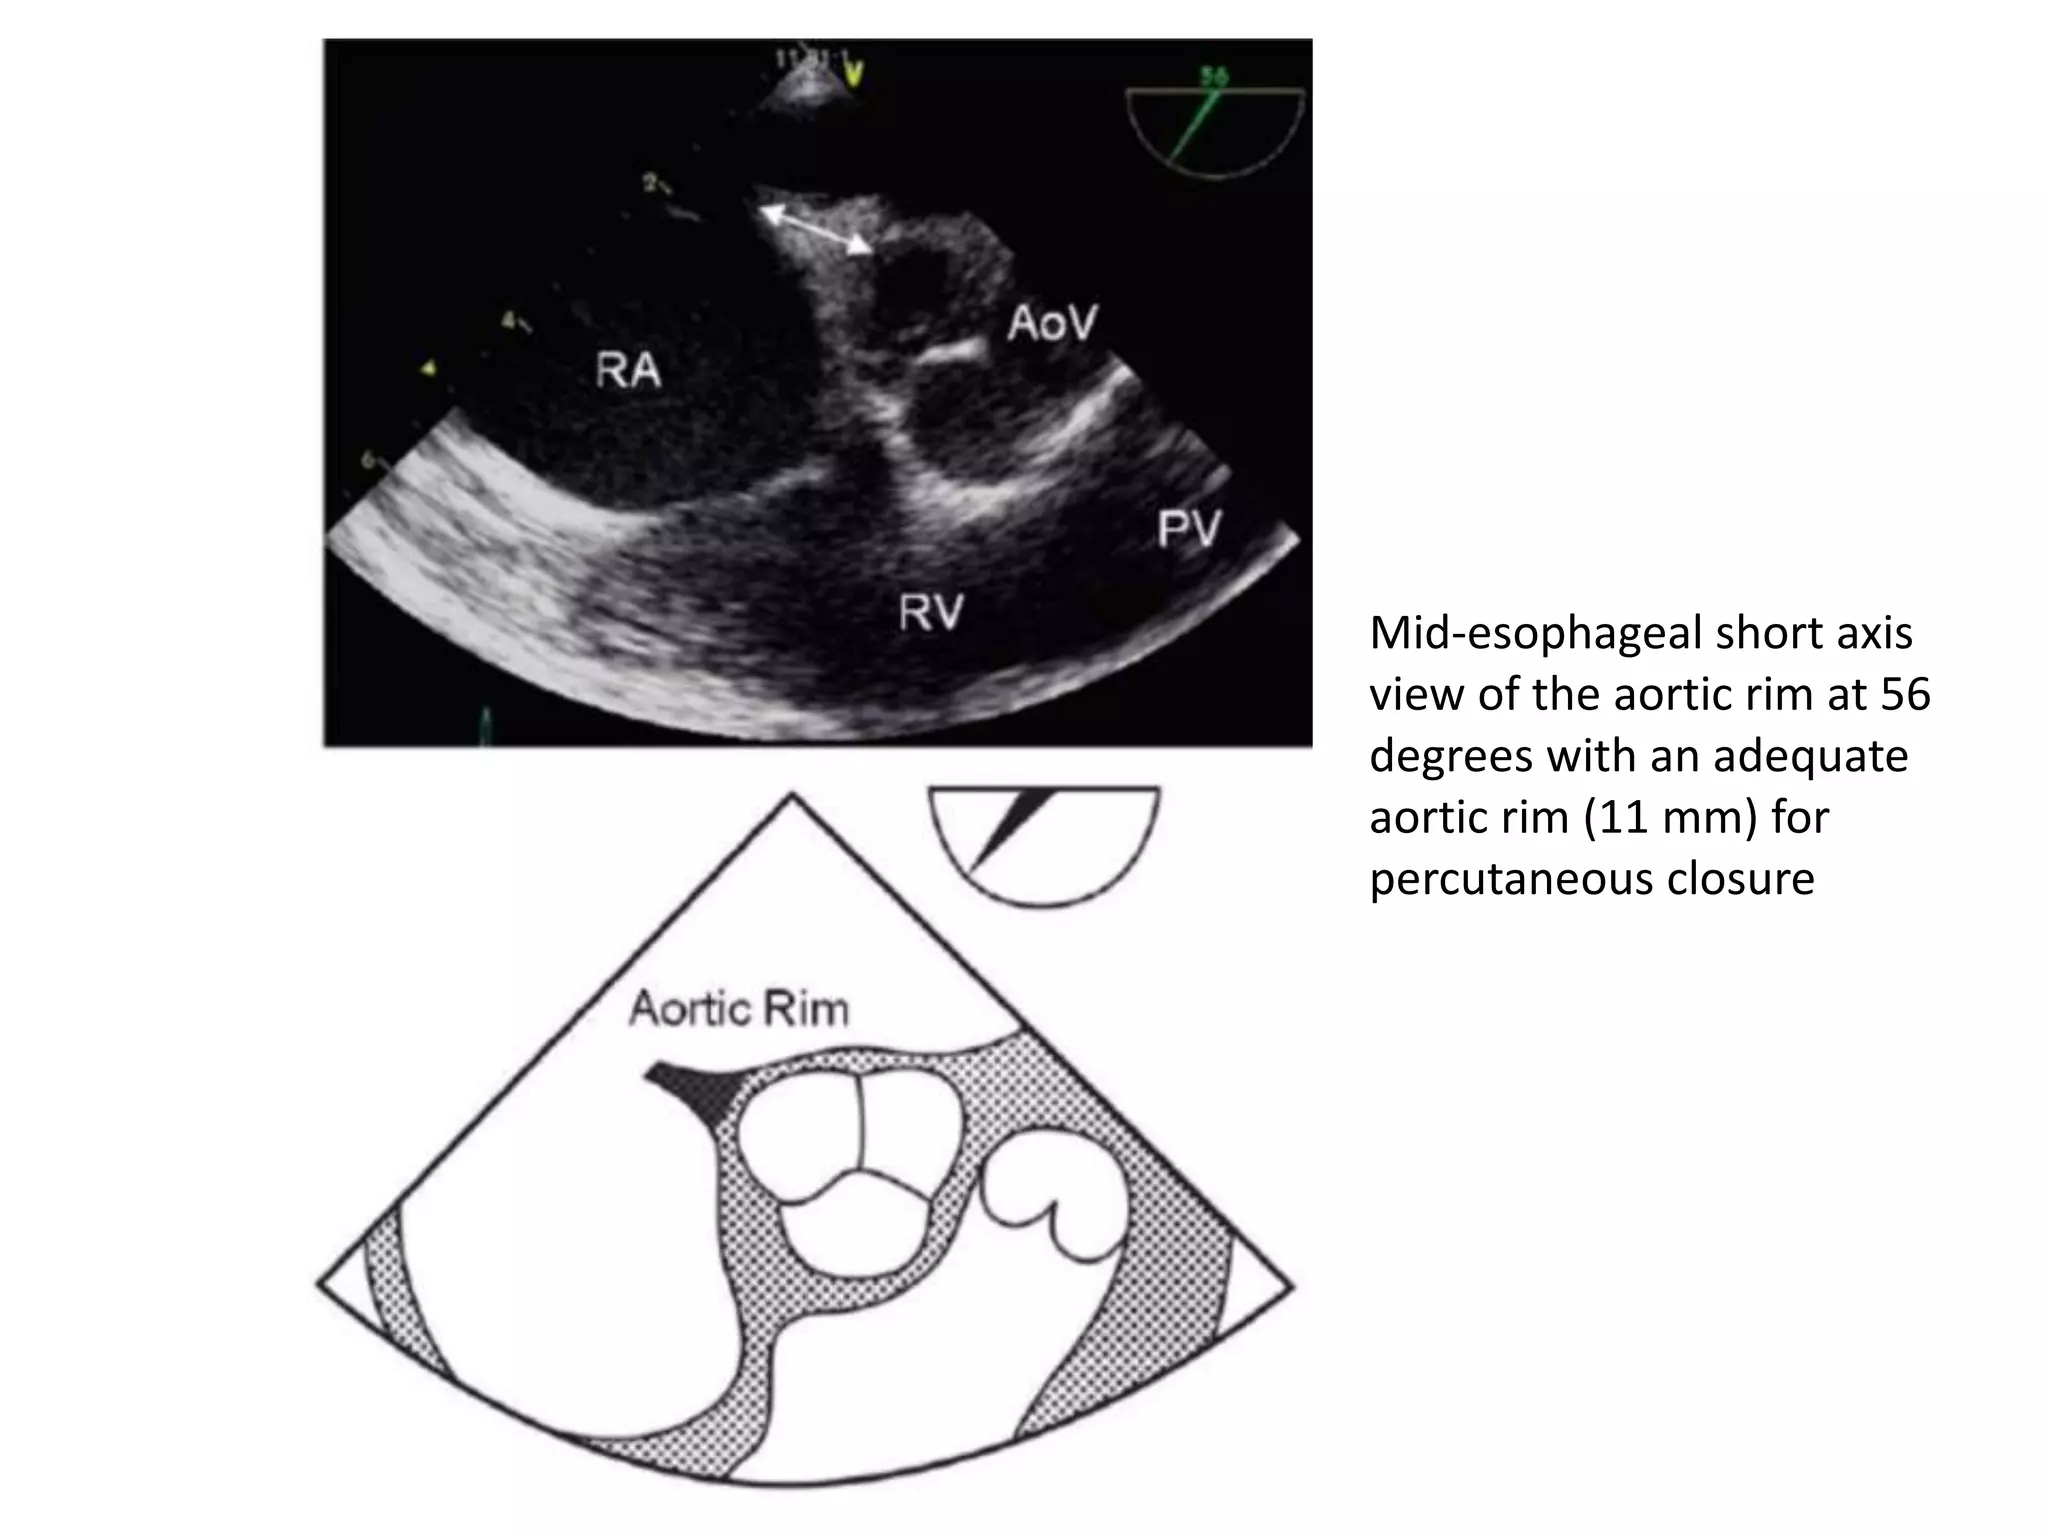

Mid-esophageal short axis

view of the aortic rim at 56

degrees with an adequate

aortic rim (11 mm) for

percutaneous closure

Mid-esophageal short axis viewof the aortic rim at 56 degrees with an adequate aortic rim (11 mm) for percutaneous closure